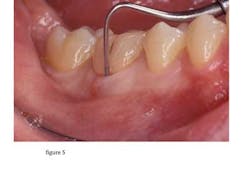

Periodontal exam

Examine the area for swelling, sinus tracts, and probing depths. In the case of a vertical fracture, a narrow periodontal pocket may be located. (Figure 5)